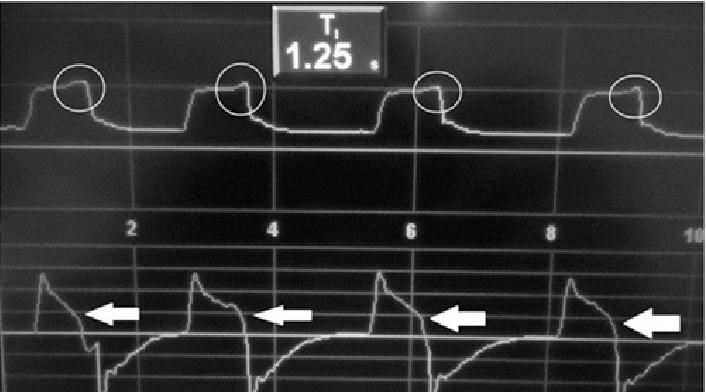

10

Q

What mode of ventilation, what type of dyssynchrony and how do you fix it?

A

Pressure control

Air-trapping, autopeep

Expiratory dyssynchrony

It’s harder to cause a trigger because increased pressure has to be overcome by the patient

Fix: Shorten I-time, increase PEEP? (not ideal)